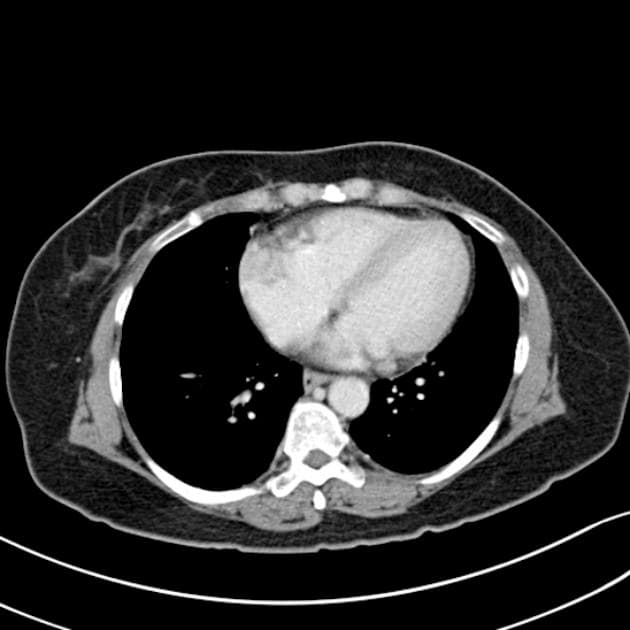

- Khối tròn, ranh giới rõ, kích thước 2,8 cm ở không gian thượng thận phải, có biến đổi dạng nang trong lòng khối. Khối này kề sát nhưng không xuất phát từ cực trên của thận phải.

Khối thượng thận phải này lần đầu được phát hiện trên hình ảnh trước sinh. Chụp hình được lặp lại vào ngày sinh, hình ảnh phù hợp nhất với u nguyên bào thần kinh sơ sinh (neonatal neuroblastoma).

U nguyên bào thần kinh sơ sinh (neonatal neuroblastoma)

U nguyên bào thần kinh sơ sinh là khối u đặc ngoài sọ phổ biến nhất ở trẻ sơ sinh, thường xuất phát từ tủy thượng thận. Bệnh thường được phát hiện trước sinh như một khối thượng thận ranh giới rõ, đôi khi có thành phần nang. Khác với xuất huyết thượng thận bẩm sinh, có thể cho thấy các đặc điểm thay đổi của tụ máu, u nguyên bào thần kinh thường ổn định hoặc phát triển và có thể xuất hiện vôi hóa trên hình ảnh theo dõi. Việc không liên quan đến thận giúp loại trừ các khối u thận nguyên phát như u Wilms. Hầu hết các trường hợp ở trẻ sơ sinh là giai đoạn thấp và có đặc điểm sinh học thuận lợi, tỷ lệ tự thoái lui cao, đặc biệt ở trẻ dưới 6 tháng tuổi. Việc định hình sớm bằng hình ảnh và theo dõi là chìa khóa để tránh các can thiệp không cần thiết.